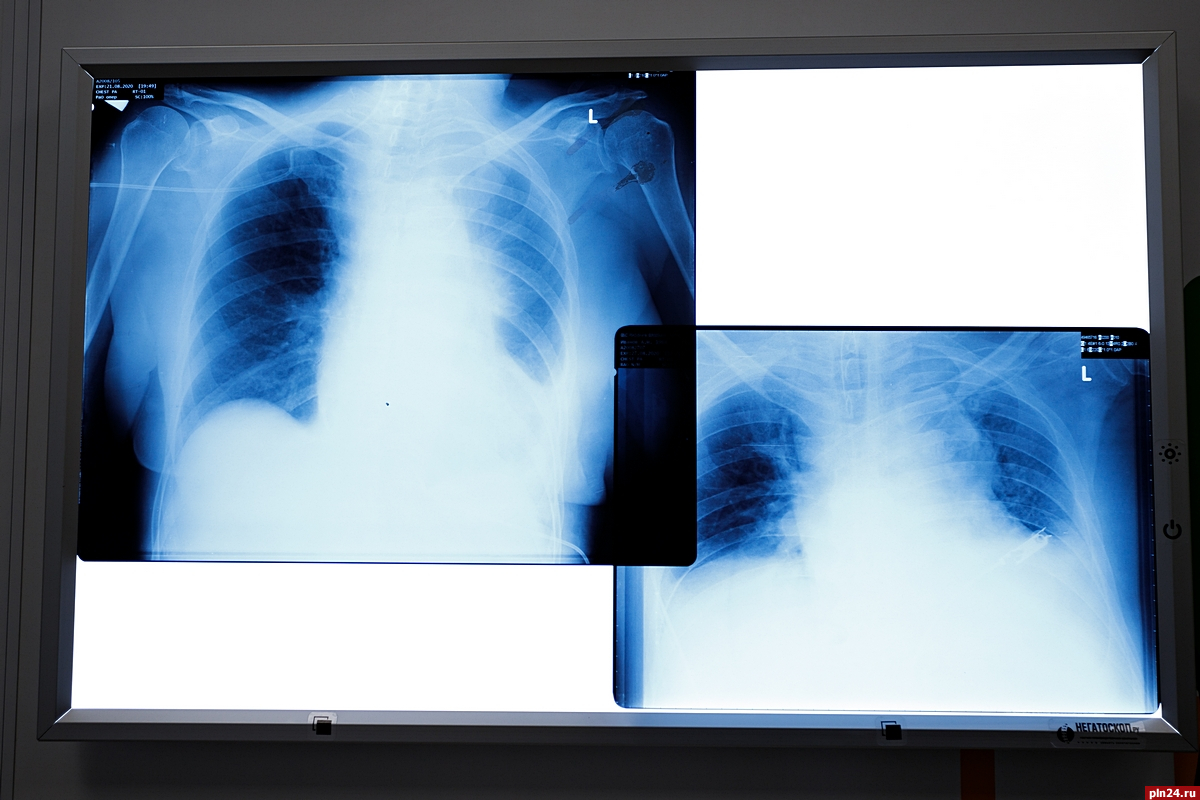

Еще 32 человека заразились коронавирусной инфекцией в Псковской области за прошедшие сутки. С начала пандемии коронавирус в регионе подтвердили у 5276 человек, пишет Telegram-канал «Официальный канал Псковской области».

За сутки от инфекции избавились 32 пациента, всего - 3964. Число летальных исходов остается неизменным - 65. Всего специалисты провели 97291 исследование на коронавирус (за сутки - 852).